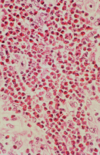

Lewy body (pathology)

- Parkinson's disease

- many other Parkinson-like syndromes

- a-synuclein, ubiquitin, neurofilaments, beta crystallin

- pale halo sign